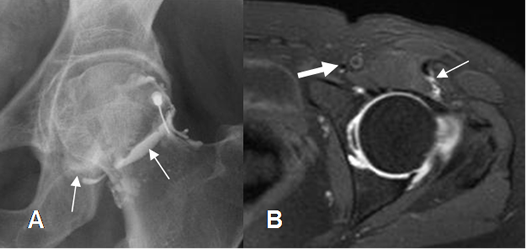

Fig 25. Técnica de ArtroRM.

A: Rx AP. Confirmación de la localización intra-articular, previo a la inyección de la mezcla de contraste. (Flechas delgadas).

B: RM axial en STIR. Mezcla intra-articular. Trayecto de la aguja dejado por el anestésico local. (Flecha delgada). Vasos femorales mediales y alejados al sitio de punción. (Flecha gruesa).